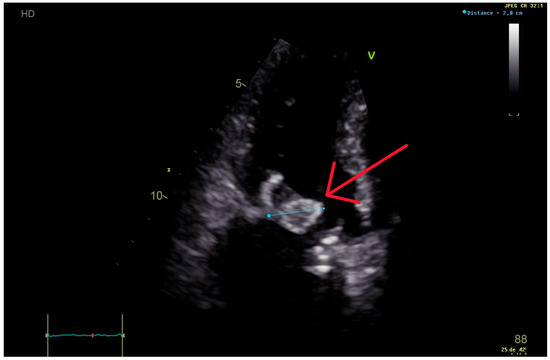

2. Case Presentation